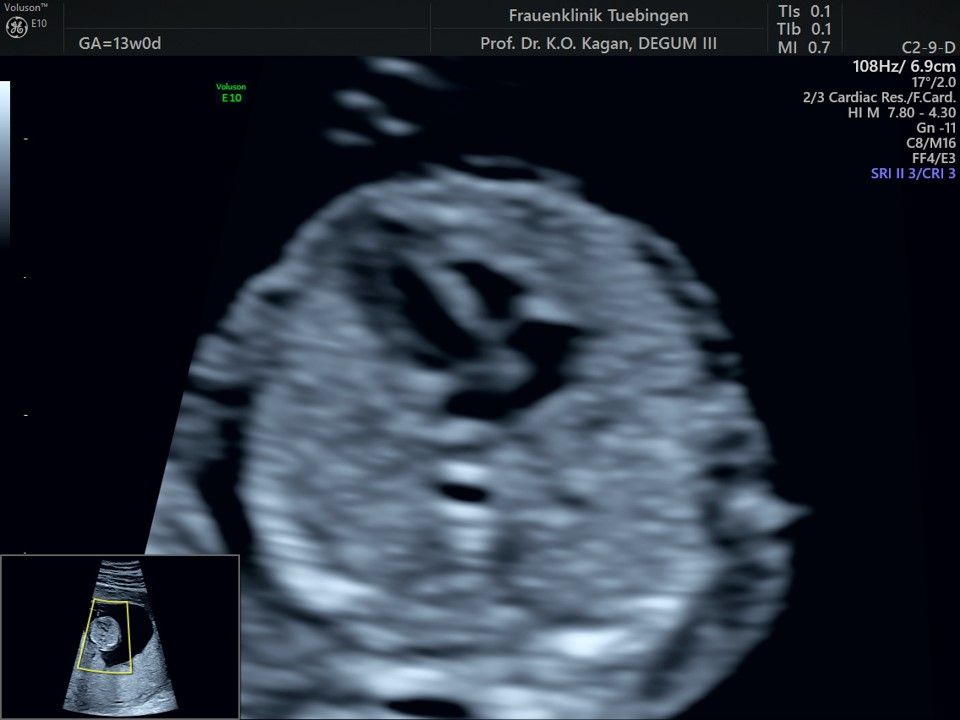

Im Rahmen des Ersttrimester-Screenings untersuchen wir die Organe des Feten mittels Ultraschall. Dabei machen wir auch gerne ein Bild für Sie.

Obwohl der Fet zu diesem Zeitpunkt erst zwischen 5 und 8cm groß ist, lassen sich bereits etwa die Hälfte aller schwerwiegenden Fehlbildungen erkennen bzw. ausschließen. Sollten wir eine Auffälligkeit sehen, werden wir mit Ihnen den Befund und das weitere Vorgehen ausführlich besprechen.

Die eigentliche Organuntersuchung findet um die 20.SSW (zweites Screening) statt. Das Ersttrimester-Screening und das zweite Screening sind sich ergänzende Untersuchungen und ersetzen sich gegenseitig nicht.

Das Ergebnis der Ultraschalluntersuchung ist wegweisend. Dabei wird der Fet vermessen, die Organe werden untersucht und die sonographischen Marker zur Risikoberechnung für Chromosomenstörungen werden beurteilt. Das sind: die Nackentransparenzdicke, Nasenbein sowie der Blutfluss in der rechten Herzhälfte und im Ductus venosus, einem Gefäß in der Leber des Feten.